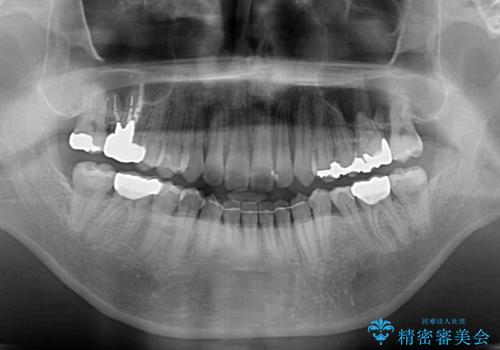

- 前歯のデコボコと、上顎前歯の突出感を気にして来院された患者様です。

通常の咬み合わせ位置と比較して、上顎の歯列が全体的に前方にある状態で、上下前歯の前後方向の位置に著しい差がありました。

上顎奥歯付近にアンカースクリューを用い、上顎歯列全体の後方移動と、大臼歯圧下を促し、前歯の上下関係を改善することとしました。

奥歯には目立つ銀歯が多くあるので、矯正治療後には下顎の銀歯をセラミッククラウンやセラミックインレーにより、補綴・修復治療することとしました。